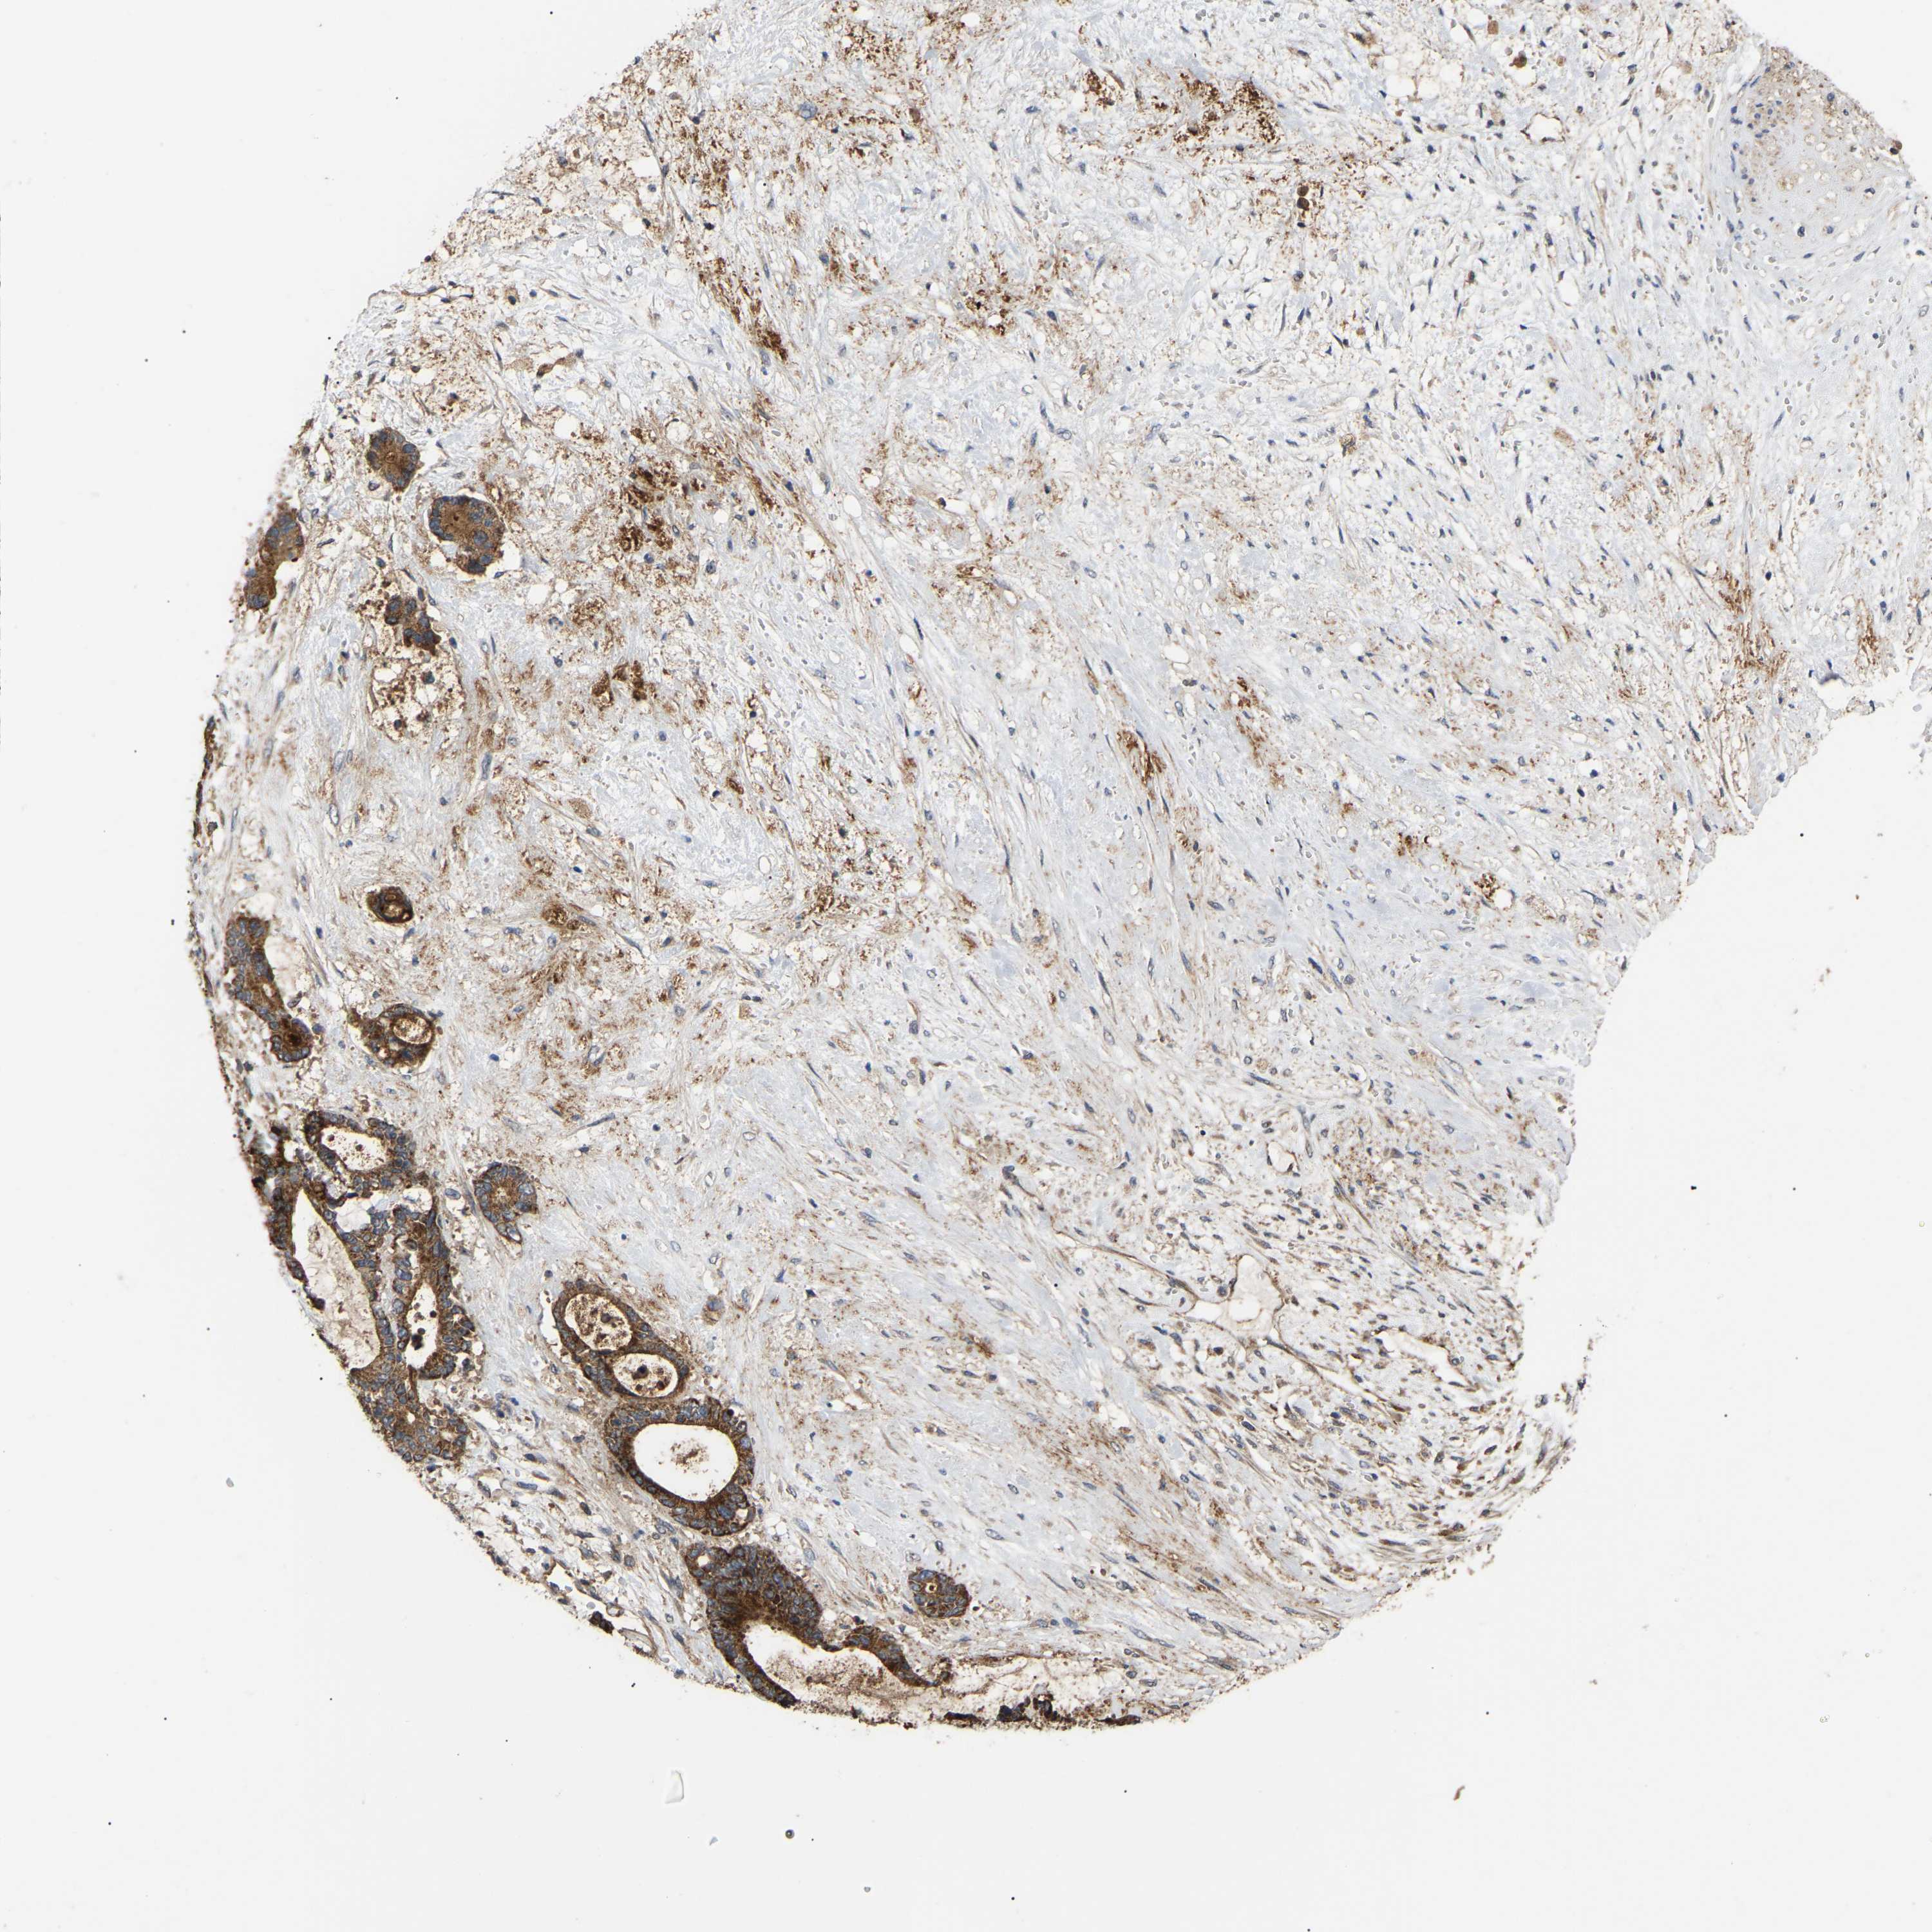

LIVER CANCER - Protein expressioni

A mouse-over function shows sample information and annotation data. Click on an image to view it in a full screen mode. Samples can be filtered based on level of antibody staining by selecting one or several of the following categories: high, medium, low and not detected. The assay and annotation is described here.

Antibody stainingi

Antibody staining in the annotated cell types in the current human tissue is reported as not detected, low, medium, or high, based on conventional immunohistochemistry profiling in selected tissues. This score is based on the combination of the staining intensity and fraction of stained cells.

Each image is clickable and will lead to virtual microscopy that enables deeper exploration of all samples and also displays staining intensity scores, fraction scores and subcellular localization as well as patient and tissue information for each sample.

Antibody HPA019369

Antibody HPA021323

Staining

High

Medium

Low

Not detected

Intensity

Strong

Moderate

Weak

Negative

Quantity

>75%

75%-25%

<25%

None

Location

Nuclear

Cytoplasmic/membranous

Cytoplasmic/membranous,nuclear

Cholangiocarcinoma

Carcinoma, Hepatocellular, NOS